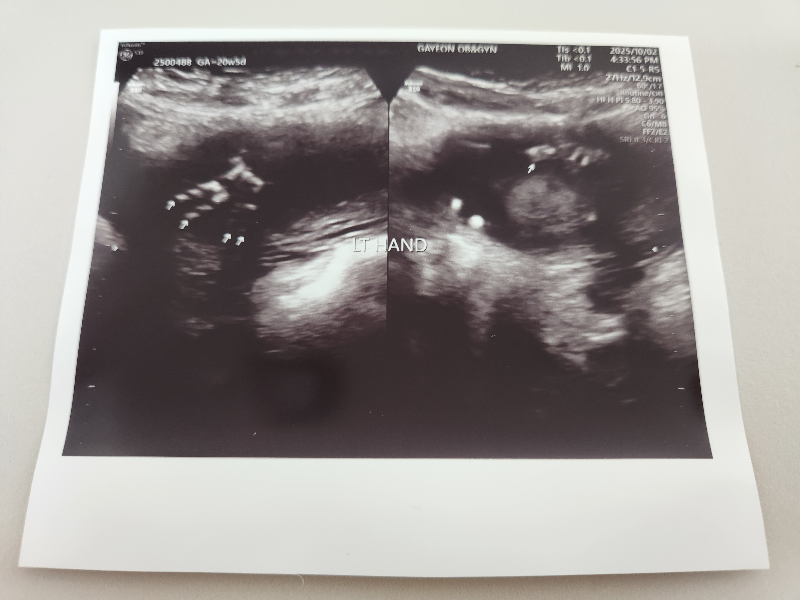

태아의 콧구멍과 입도 확인합니다.

태아의 눈도 확인합니다.

2차 정밀 초음파는 입체로도 봐주십니다.

태아가 손을 올리고 있어서 잘 안 찍혔지만, 이제 사람이 된 것 같습니다.